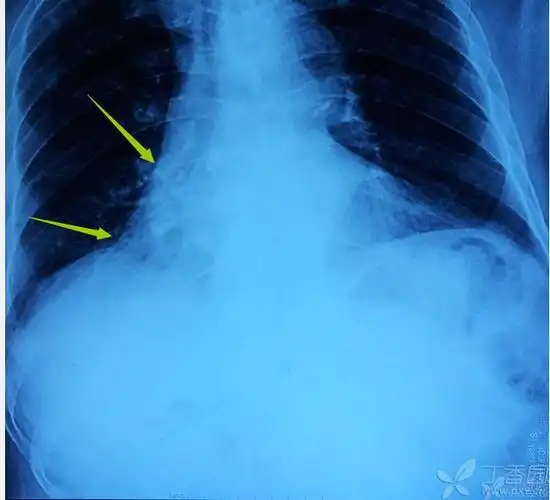

注意右侧心膈角,右下叶不张 的诊断成立.影像科的大夫会看图说话